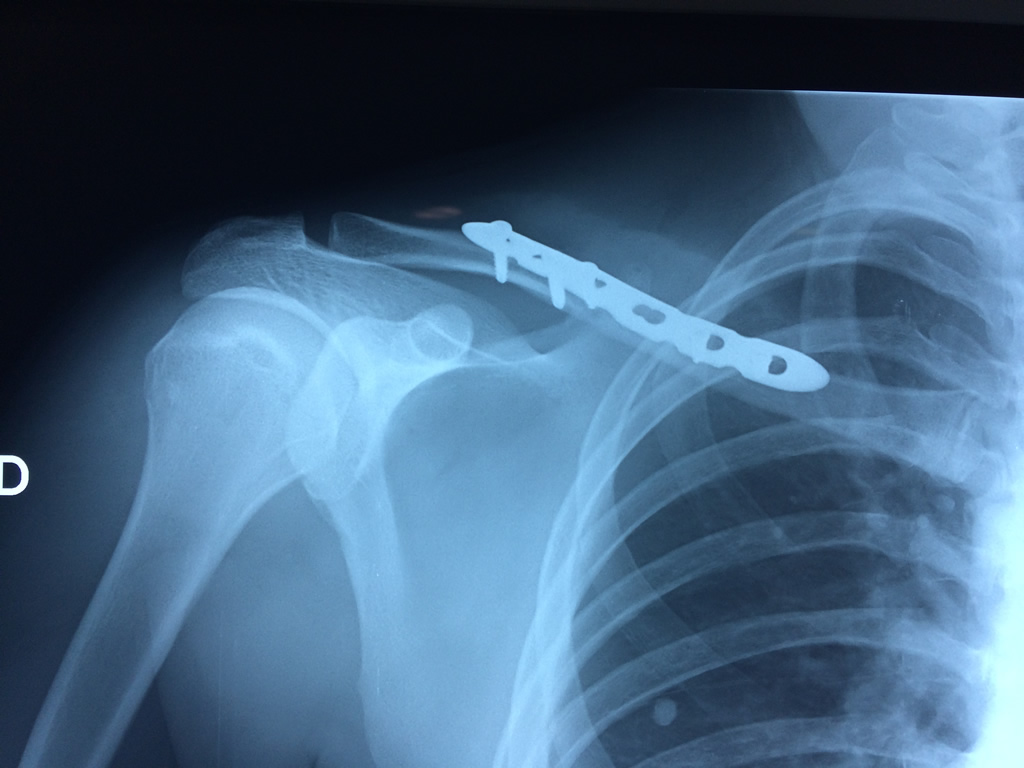

Cirugias en El Salvador - Clavícula

La clavícula es un hueso largo, con forma de "S" itálica, situado en la parte anterosuperior del tórax. Junto con la escápula forman la cintura escapular. Se puede palpar por toda su longitud y se extiende del esternón al acromion de la escápula, siguiendo una dirección oblicua lateral y posterior.